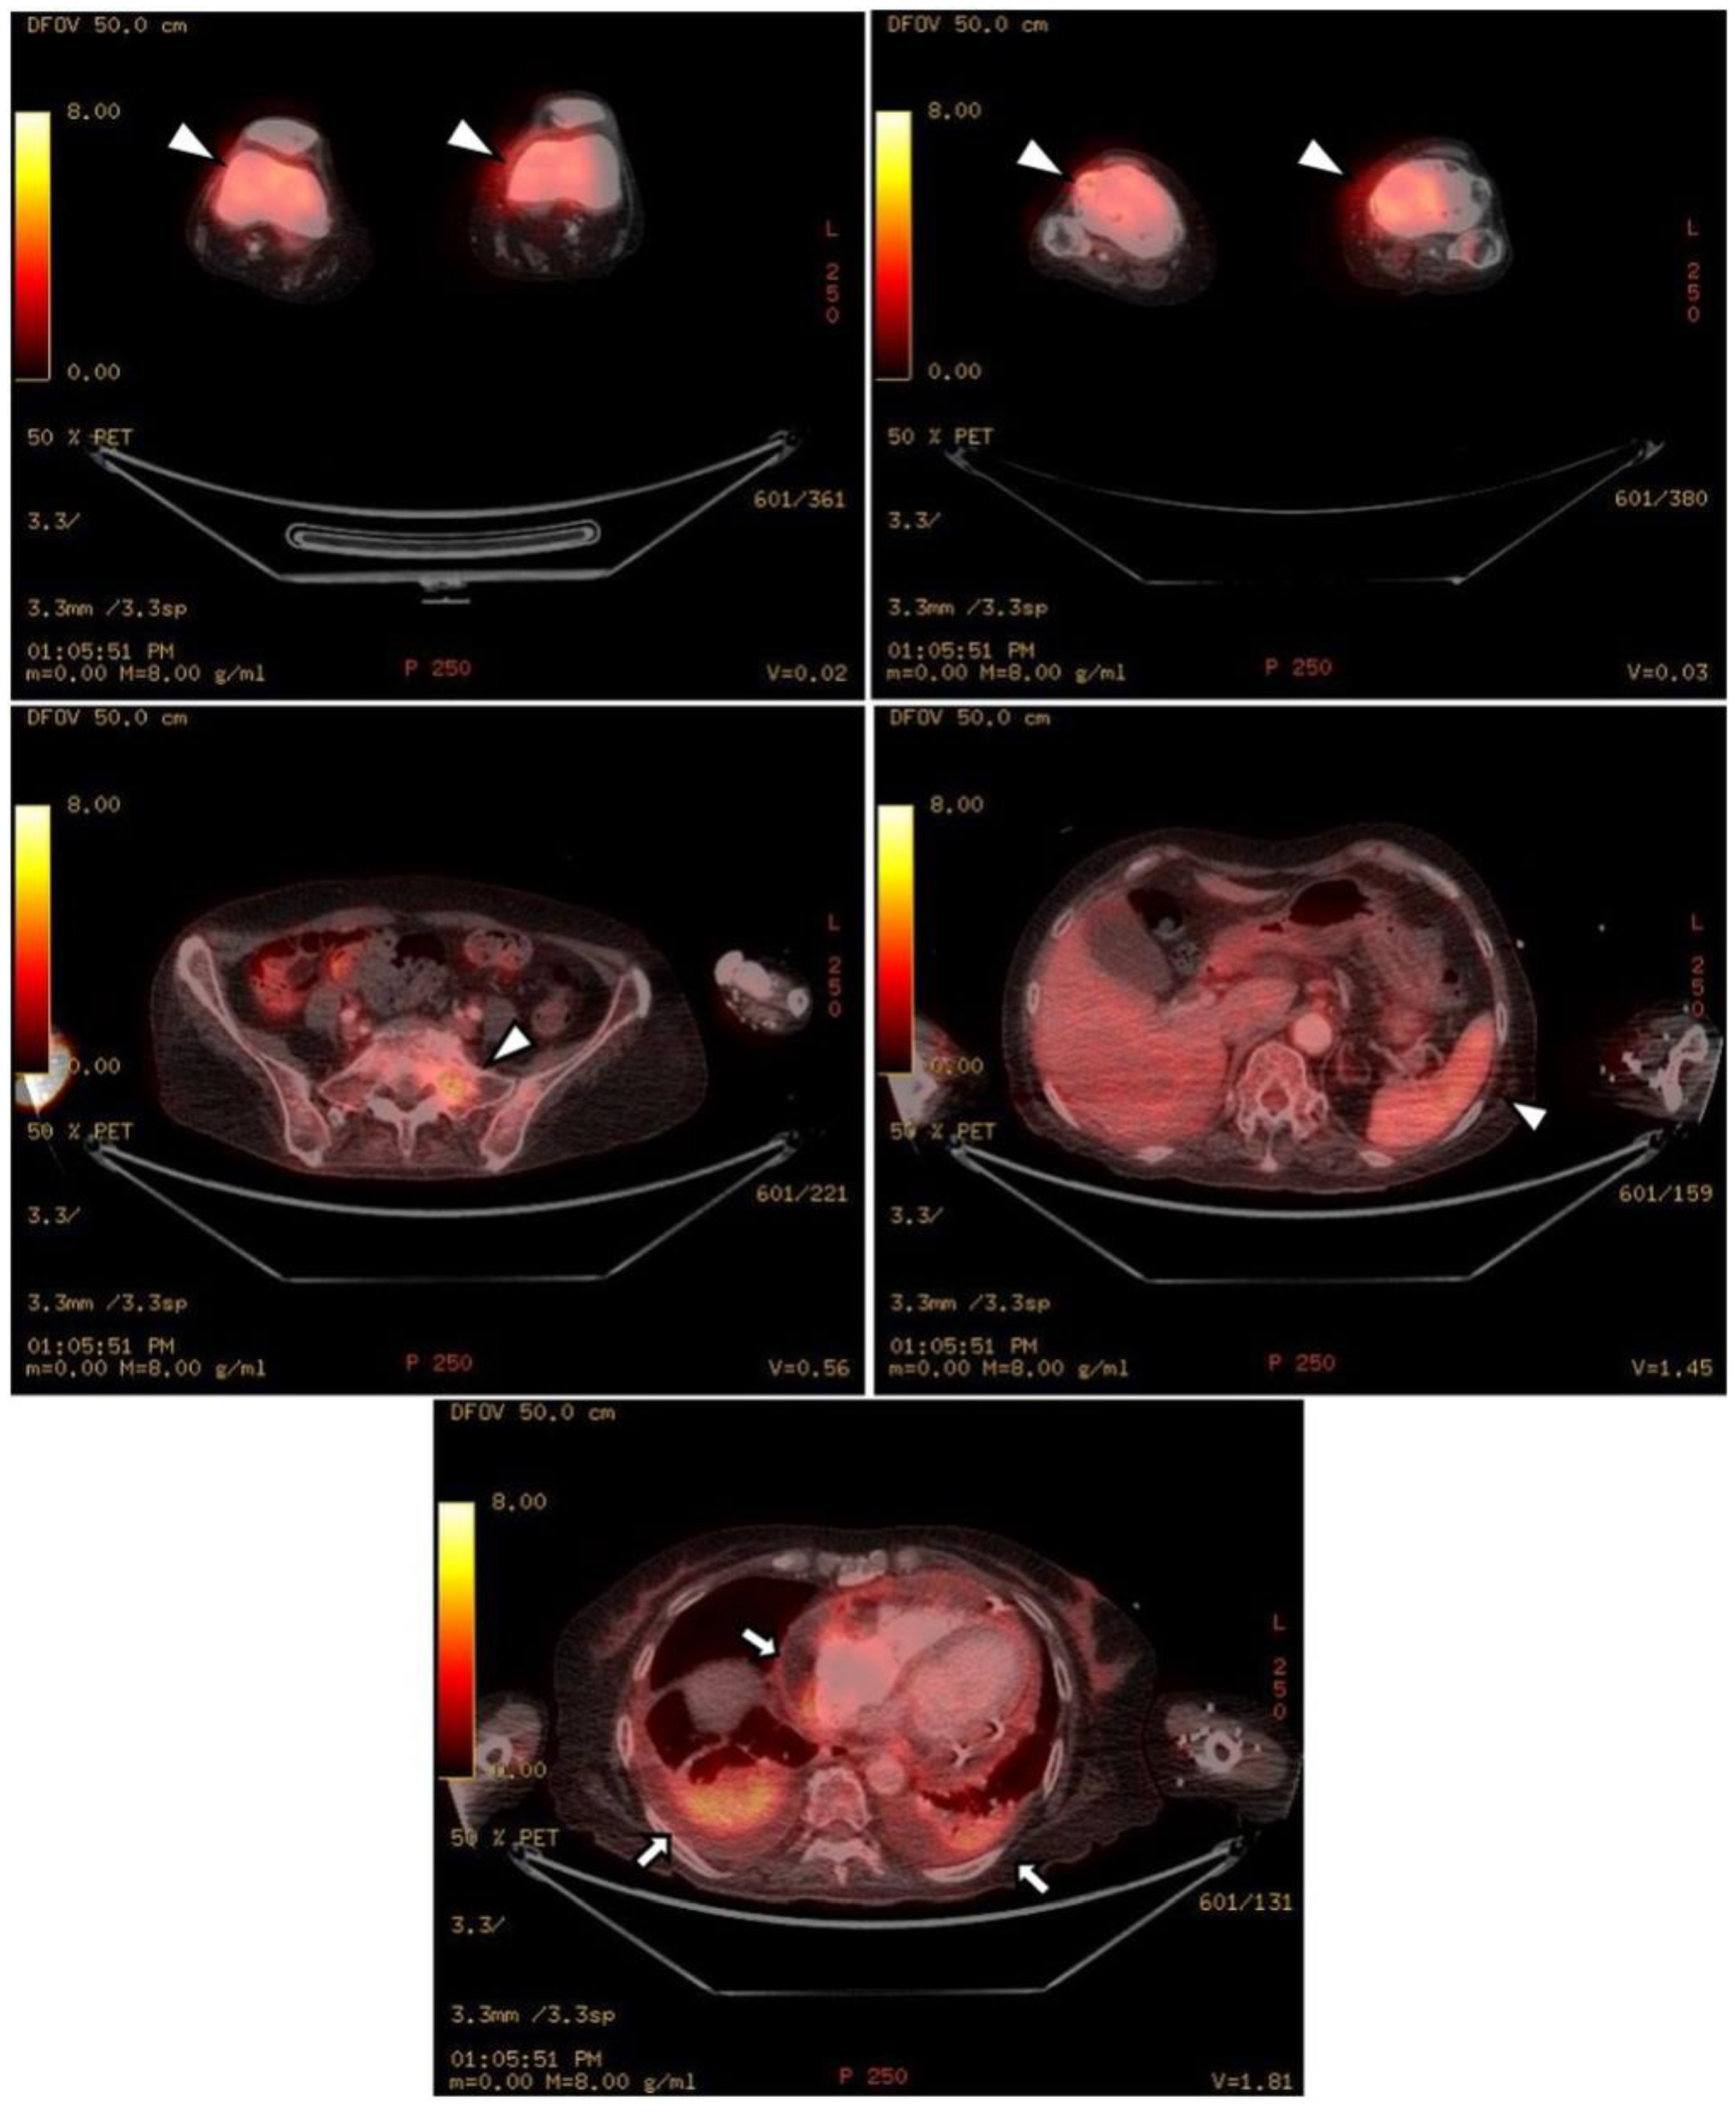

The chest CT showed notable pericardial effusion with pericardial enhancement and pleural effusion with pleural enhancement (Figure 2). The abdominal CT showed fluid collection in both perirenal spaces and diffuse infiltration in both kidneys (Figure 3). Pericardial biopsy revealed chronic active inflammation with nonspecific findings. The PET/CT showed increased uptake in the sacrum, distal femur, proximal tibia, and spleen, with pericardial and pleural effusion (Figure 4). The simple radiography and MRI of the left knee showed patchy sclerotic changes in the medulla of the distal femur and proximal tibia (Figure 1).

Figure 4.

Upon PET-CT, there is diffuse FDG uptake in both distal femurs, proximal tibia, sacrum, and spleen, which shows increased metabolic activity (white arrowheads). As shown in the chest and abdominal CT, there is pericardial effusion and pleural effusion shown by FDG uptake in the pericardium and pleura (black arrows).